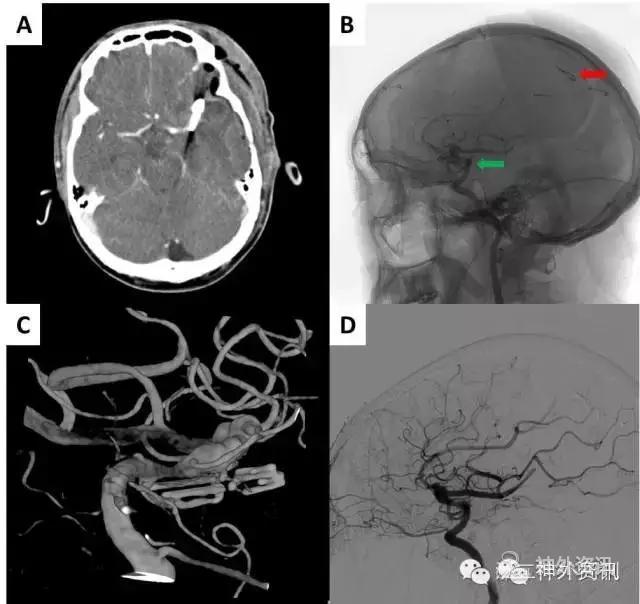

依据动脉瘤与AVM关系,一般可以分为四类:I型,两者完全独立,动脉瘤与AVM位于不同的血管上;IIa型,血流相关动脉瘤,动脉瘤位于颅内大血管分叉部近端,且AVM由该血管供血;IIb型,血流相关动脉瘤,动脉瘤位于畸形血管团直接供血动脉上,或位于类型IIa中颅内大血管的远端;III型,动脉瘤位于畸形血管团上[1]。具体如图8所示。

图8. 伴发动脉瘤的AVM分类方式(图片摘自FLORES BC)。A. I型;B. IIa型;C. IIb型;D. III型